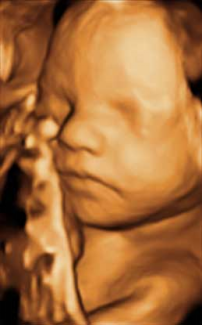

Feto de 29 Semanas